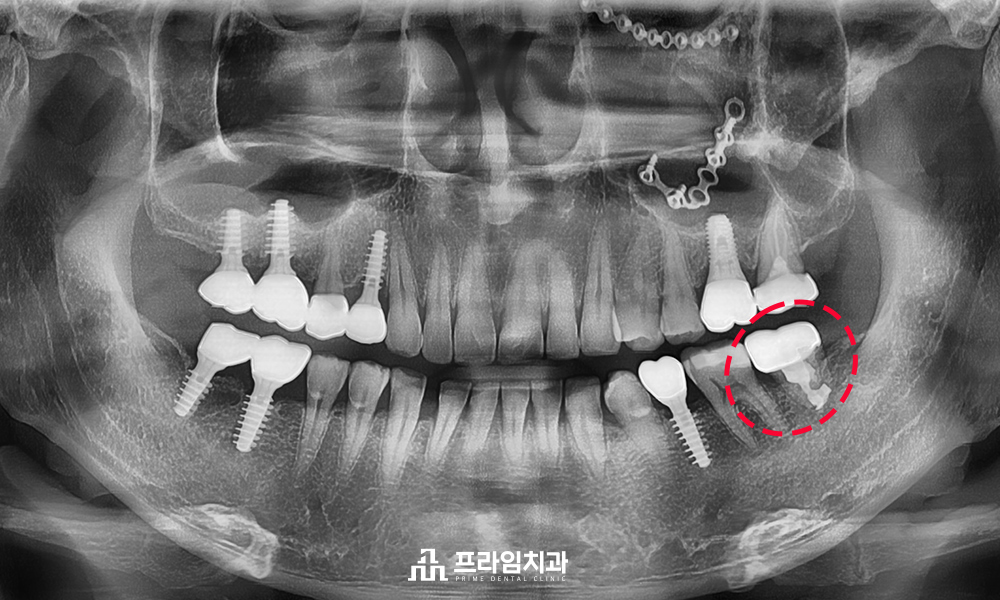

사랑니를 어금니 부위에

이식하여 크라운 치료를 한 뒤

5년이 지나고 난 후에도

문제없이 사용하고 계셨는데요.

환.자분께서는 하나의 치아라도

살려서 건강하게 사용하실 수 있음에

만족도가 매우 높으셨습니다.